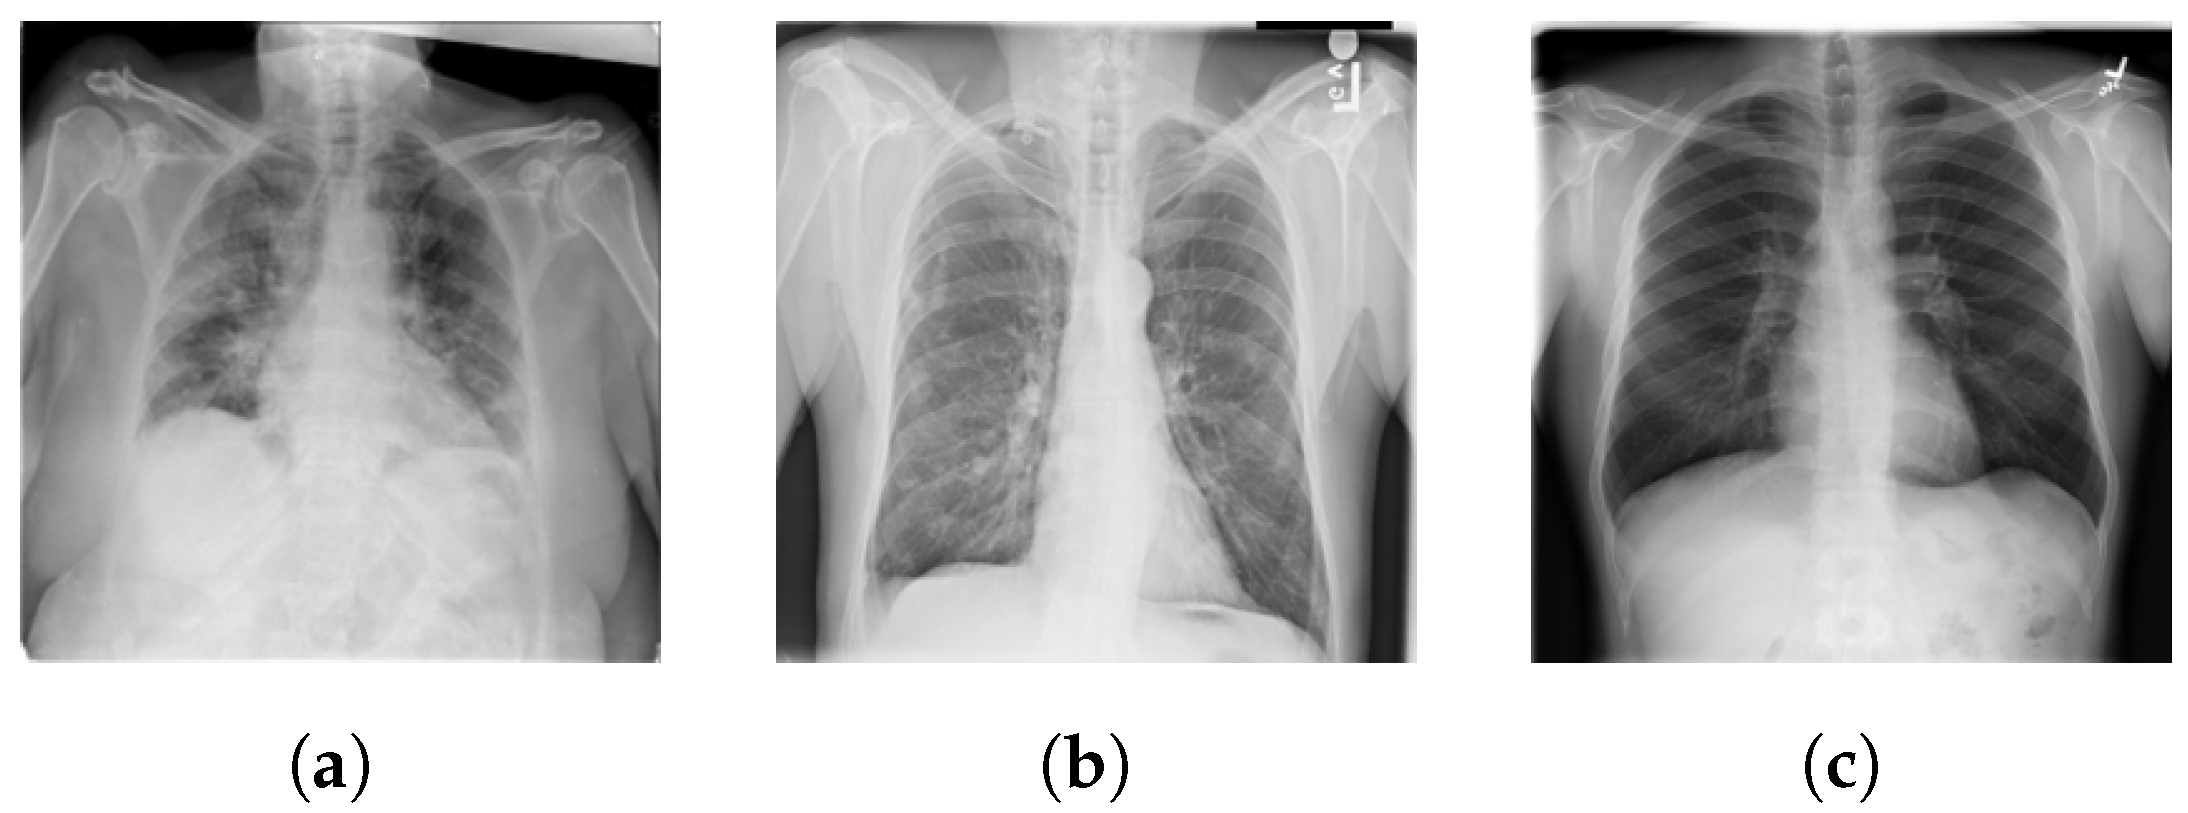

In our experimental setup, we used an unbalanced case by taking a subset of samples from the above dataset to test the system’s robustness in scenarios where images are acquired under specific settings. The resilience and efficacy of our system were rigorously evaluated using this imbalanced dataset, ensuring its applicability across diverse image settings and scenarios. The dataset, along with the associated codes and experiments, are made publicly available for further research and validation purposes. Table 1 illustrates each class’s total number of samples. Figure 2 shows a sample CXR image for each class.

Sample CXR images: (a) COVID-19. (b) Non-COVID-19. (c) Normal.